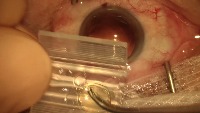

eye detetction Computer Vision Project

Classes (10)

三角刀

人工晶体定位勾

开睑器

无损伤镊

晶体植入镊

注吸器

虹膜恢复器

角膜穿刺刀

超声乳化调节杆

超声乳化针头